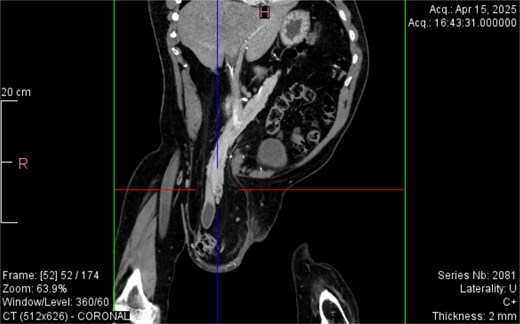

From the provided coronal CT image (Fig. 1), the following findings are noted: The spinal curvature is prominently right-convex in the lumbar region, indicating a dextroscoliosis with marked rotation of vertebral bodies, causing asymmetrical displacement of the retroperitoneal organs. The curvature shortens the abdominal cavity vertically on the left side, while expanding the retroperitoneal volume on the right. The right femoral head is elevated and laterally displaced, consistent with developmental dysplasia of the hip. There is flattening of the acetabulum and apparent false articulation with the iliac wing. These findings suggest chronic alteration of pelvic symmetry with pelvic tilt and subsequent uneven distribution of abdominal and intra-pelvic pressure. The combined effects of spinal curvature and pelvic deformity create an aberrant vector of force and organ positioning, contributing to the downward displacement of the pancreas and duodenum.

CT imaging (Figs 2–5) revealed a right inguinal hernia containing small bowel loops, ascending colon, the second and third portions of the duodenum, and the pancreatic head. The pancreatic head appeared rotated and displaced inferiorly into the hernia sac, without signs of acute pancreatitis.

Dextroscoliosis with marked rotation of vertebral bodies, displaced right femoral head and giant inguinal hernia.